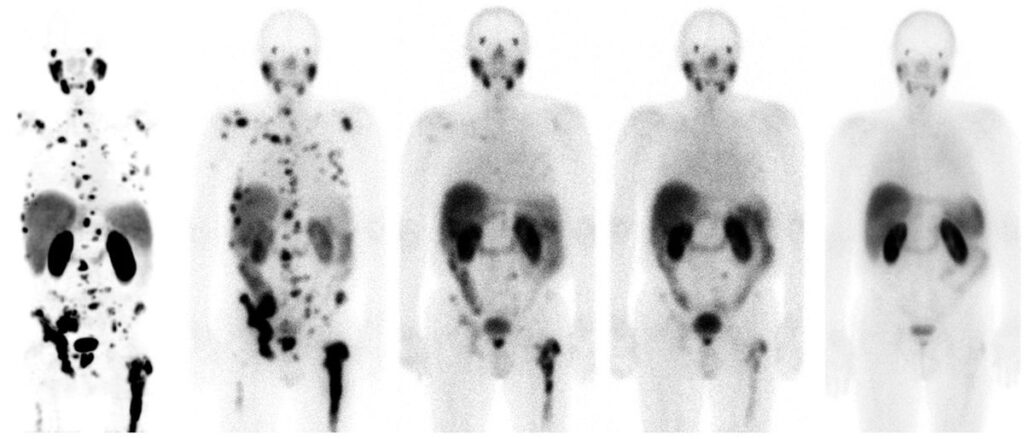

El médico José Luis Carreras se entusiasma cuando habla de la teragnosis, una pujante estrategia que funciona como un misil de precisión contra las células de algunos tipos de cáncer. Carreras, jefe de Medicina Nuclear en el Hospital Clínico San Carlos, en Madrid, habla de “resultados espectaculares” en determinados pacientes terminales. El médico recuerda el caso de un hombre alemán de 62 años, con cáncer de próstata y una diseminación masiva con metástasis en los huesos. Tras un tratamiento experimental con teragnosis en la Clínica Central de Bad Berka (Alemania), ocho meses después parecía limpio. Volvió a trabajar y a hacer deporte. Y tres años y medio después seguía libre de cáncer, según explicó Carreras en febrero en una sesión científica en la Real Academia Nacional de Medicina, en Madrid.

El médico Michael Morris, del Centro Oncológico Memorial Sloan Kettering, en Nueva York, ha presentado en el congreso de ASCO los últimos resultados de la teragnosis contra el cáncer de próstata avanzado. La técnica consiste en utilizar una molécula con alta afinidad por la PSMA, que es una proteína que suele estar en grandes cantidades en las células del cáncer de próstata. Para hacer el diagnóstico, esa molécula afín al PSMA se une a un elemento químico radiactivo, el galio-68, que brilla en una exploración con tomografía por emisión de positrones (PET). Para el tratamiento, la misma molécula se une a otro elemento químico, el lutecio-177, que emite una radiación local que mata a las células cancerosas. Es como disparar primero una flecha con una bombilla y después otra flecha con una pequeña carga explosiva.

En el ensayo de Morris participaron 831 pacientes con cáncer de próstata resistente a la castración y metástasis, un tipo de tumor habitualmente letal. Los enfermos que recibieron el tratamiento con teragnosis vivieron 15,3 meses, frente a los 11,3 meses de los hombres a los que se administró una terapia estándar. Cuatro meses de diferencia —un 35% más— pueden parecer poca cosa, pero se trataba de pacientes prácticamente desahuciados, en los que ya habían fallado la quimioterapia y los tratamientos hormonales.